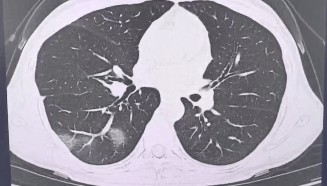

查出流感没在意,女子硬扛三天后肺都“白”了……

流感不过是一场“重感冒” 吃点药休息休息就能好? 浙江杭州39岁的程女士(化姓)是名“工作狂”, 经...